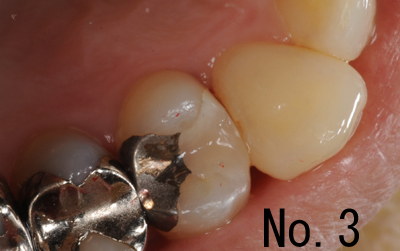

下記の画像は、保険診療であり、直接口腔内で充填処置をしたものです。No.2とNo.3は同一歯で近心のみの修復完了の画像で、途中です。保険での診療が主ですので、写真を撮り忘れて(撮っている時間がないことが多い)しまってることがほとんどです。日常的な治療方法と言えるでしょう。